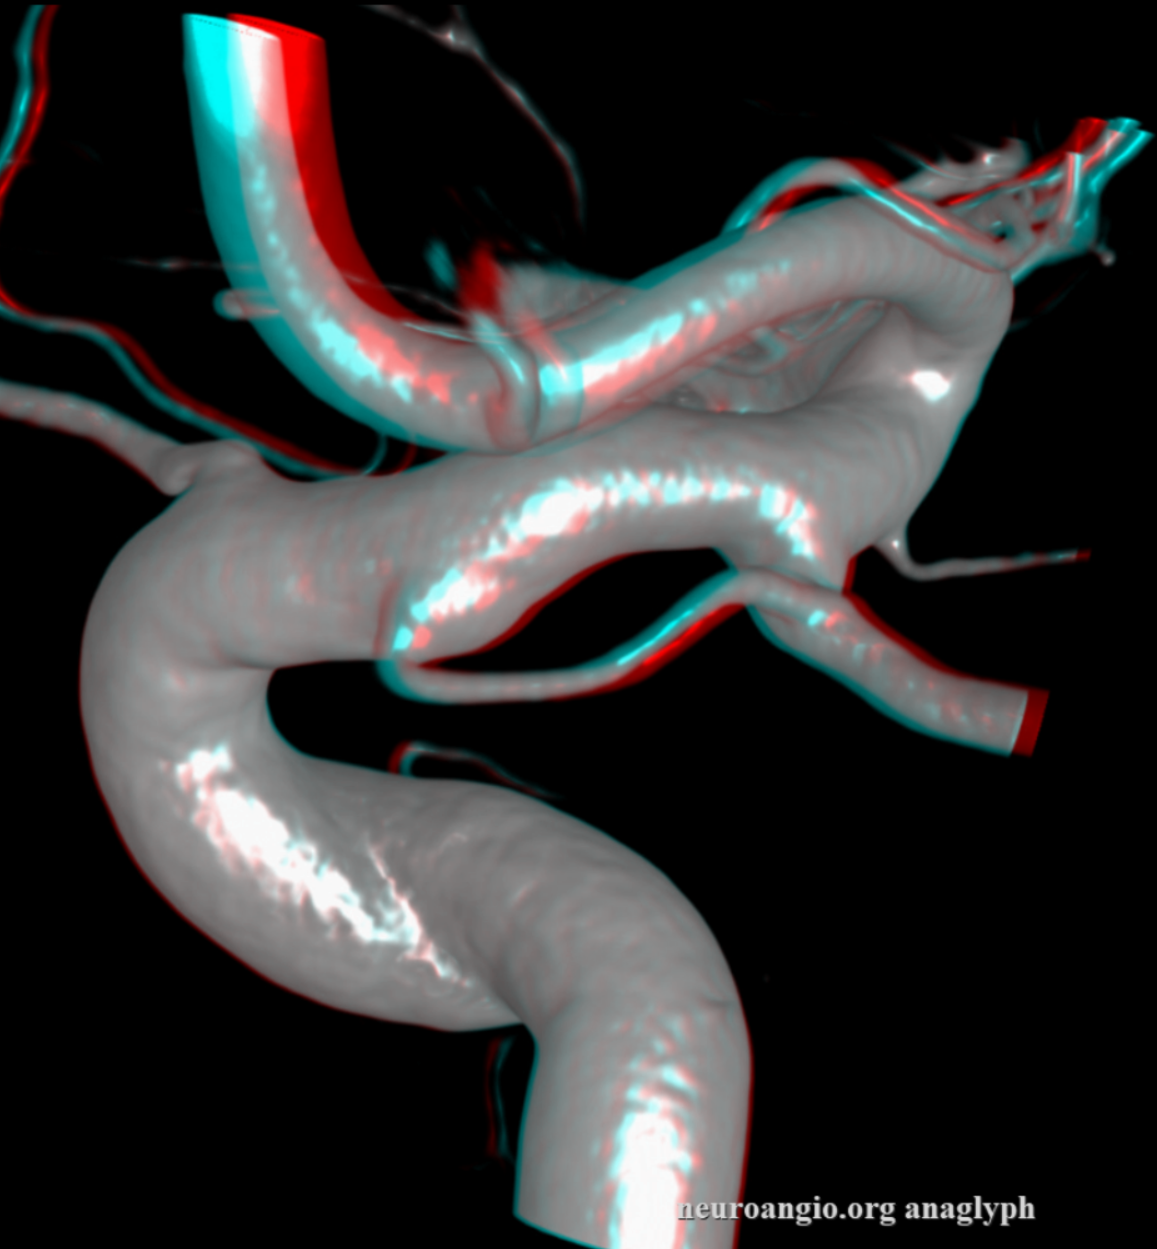

Stereos and MIPs. Both superior and inferior hypophyseals are well seen. The superior hypophyseal, despite being invisible on standard issue views, is quite large, even having two branches to the hypophysis.

Case courtesy Dr. Eytan Raz — here is a beautiful example of a very dominant superior hypophyseal artery (arrow) supplying the posterior hypophysis (arrowhead), with a correspondingly small inferior hypophyseal contribution from the MHT (dashed arrow)

Cross eye stereo

View from the back — again small inferior hypophyseal, big superior hypophyseal — balance again… See the beautiful vascular ring of the posterior pituitary — the connecting it with the contralateral side

Cross-eye stereo

MIP image shows the sella nicely — and helps prove its posterior pituitary

Of course, there is an aneurysm here — the branch point camp would point out how this larger than usual branch is a setup for aneurysmal formation. Naturally…